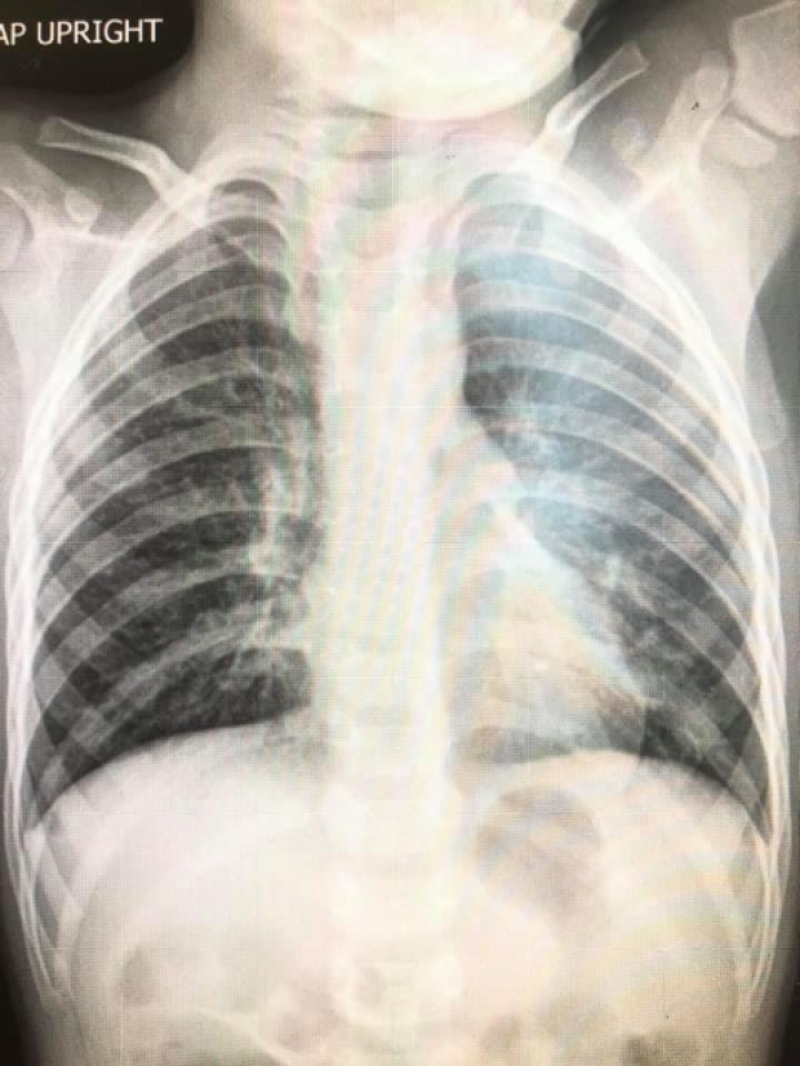

ด่วน เปิดภาพปอดจากผู้ป่วย ไวรัส RSV ปอดเเหว่งเป็นเเถบ

วันนี้ ( 6 พ.ย. 63 )เพจ Infectious ง่ายนิดเดียว ได้เปิดเผยภาพฟิล์มเอ็กซเรย์ปอด เด็กที่มี อาการจาก ไวรัส RSV พร้อมระบุข้อความว่า

" รวมฟิล์มปอดเด็กที่มีอาการจาก ไวรัส RSV 10 คน ที่แอดมิดวินิจฉัยหลอดลมอักเสบ ปอดอักเสบ

เปิดภาพปอดจากเด็กที่ป่วย ไวรัส RSV ชี้ทำหลอดลม-ปอดอักเสบ